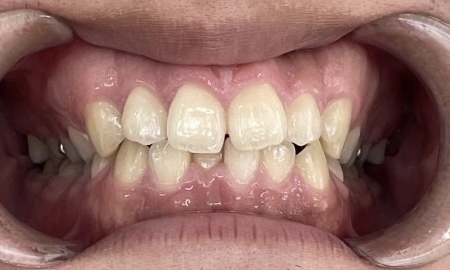

Before

After

矯正の種類 / invisalign GO

年齢・性別 / 30代男性

主訴  /  下の歯の叢生、オーバージェット、交叉咬合

治療期間 / 12ヶ月

費用 / 簡易検査 5,000円(税別) 精密検査 30,000円(税別)

両額マウスピース 450,000円(税別) 両額リテイナー料 40,000円(税別)

※マウスピース交換時別途調節料5,000円(税別)

副作用 / 口内炎・歯の移動に伴う痛み・知覚過敏 ※数日で収まる場合が多いです

リスク / 後戻り防止の為、夜のみマウスピースで保定を指示